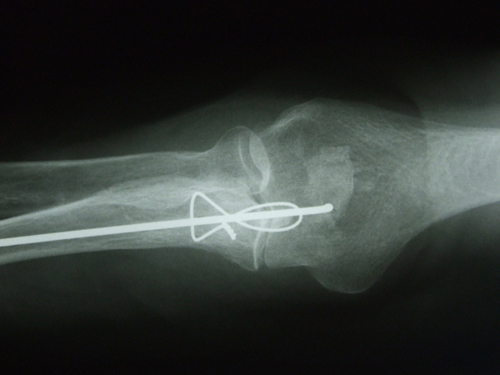

Fractura supracondílea de codo. Tratamiento con agujas.